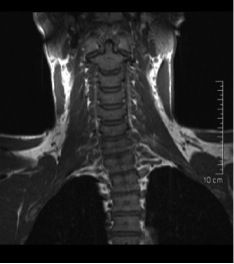

Das Iliosakralgelenk, kurz ISG, ist ein tragendes zentrales Gelenk im menschlichen Körper, das die untere Wirbelsäule mit dem Becken verbindet. Seine Hauptfunktion besteht darin, Kraft vom Oberkörper auf die Beine zu übertragen, Rumpf und Extremitäten zu einer funktionellen Einheit zu verbinden, und diese zu stabilisieren, was es für alltägliche Bewegungen unentbehrlich macht. Häufige Krankheitsbilder wie die ISG-Blockade oder -Entzündung können seine Funktion jedoch erheblich beeinträchtigen. Die strahlenfreie Magnetresonanztomographie des ISG, kurz MRT ISG, ist ein zuverlässiges und nicht invasives Verfahren zur Diagnostik solcher Erkrankungen.

Eine MRT des ISG bietet entscheidende Vorteile. Als nicht invasive Methode ist sie sicher, schmerzfrei und komfortabel. Sie liefert detaillierte Bilder von Weichteilstrukturen und Gelenken, die mit anderen Methoden wie Röntgen nicht sichtbar sind. Dadurch ermöglicht sie eine gründliche Beurteilung des Iliosakralgelenks und seiner Umgebung. Mit der Fähigkeit, eine Vielzahl von Pathologien zu identifizieren, ist die MRT des Iliosakralgelenks ein unschätzbares Werkzeug für die Diagnose und Behandlungsplanung.

Fettunterdrückte Sequenzen, z.B.T2 STIR (Short TI Inversion Recovery) sind spezielle Techniken in der MRT-Bildgebung, die eine bessere Darstellung von entzündlichen Prozessen ermöglichen. Dabei werden die unterschiedlichen Erholungs- bzw. Wiederherstellungszeiten (Relaxationszeiten) verschiedener Gewebetypen genutzt, um eine differenzierte Darstellung zu ermöglichen.

Das geschieht, indem Fettgewebe unterdrückt wird, also dunkel abgebildet wird, wodurch dann wiederum die Signale von Flüssigkeiten, wie sie bei Entzündungsreaktionen vermehrt auftreten, besser zur Geltung kommen. Bei der MRT des Iliosakralgelenks kann diese Technik besonders hilfreich sein, wenn der Verdacht auf eine Entzündung des ISG besteht.